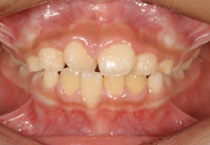

Anterior Crossbite

Case 1

Smile Line case 1 2022.06.14

2022.06.14